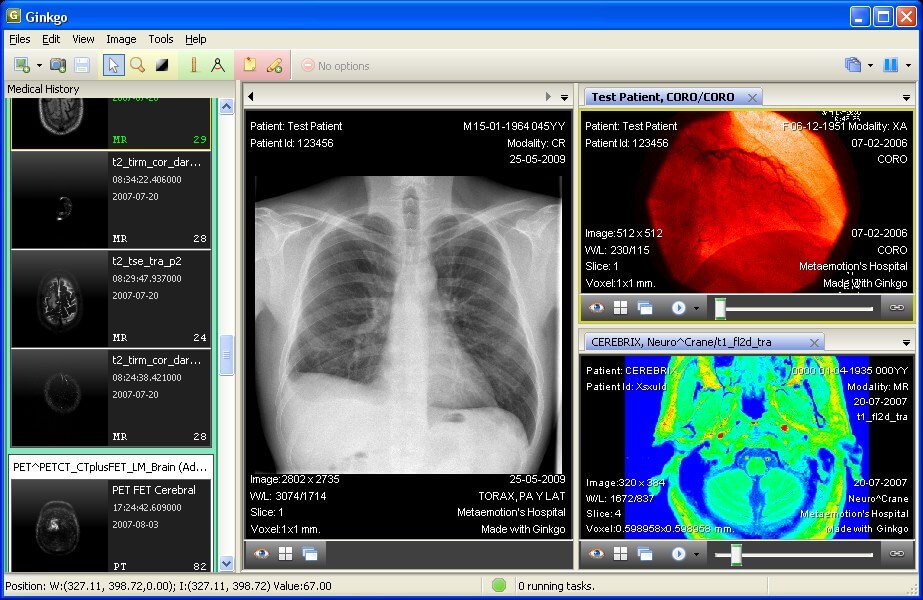

This is one of the few viewers that is compatible with Windows, Mac OS X, and Linux. It is an open source project that supports PACS. It has all the standard DICOM tools, but not many of the advanced tools required in medical diagnosis and research. The Pro version has advanced features like MPR and MIP.